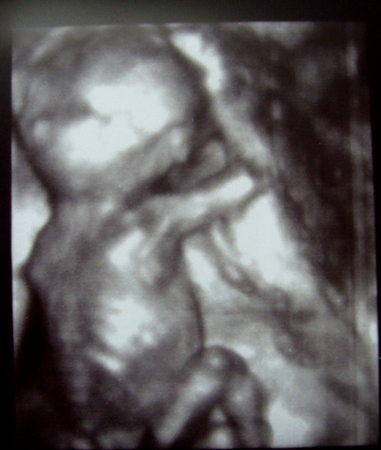

Все у нас отлично! Развиваемся хорошо, на недельку вышли вперед по параметрам. Сердечко бьется ритмично.

Плацента 0 ст.зрелости, 20мм.

Малыш лежит головкой вниз все-таки!

А вот личико прятал)) Прикрывал ручкой, тер глазки.